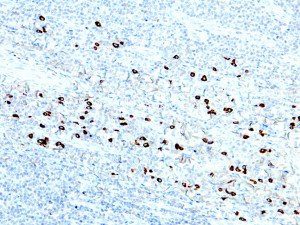

It is the ICU physician who is most likely to witness one of the deadliest manifestations of the abnormal immunological response, the cytokine storm syndrome (CSS). This response is also referred to by some as the cytokine release syndrome (CRS). CSS is characterized by continuous activation and expansion of macrophage and lymphocyte populations, which secrete large amounts of cytokines, causing the cytokine storm. This massive cytokine release is akin to hemophagocytic lymphohistiocytosis (HLH) disease, a syndrome characterized by initial unchecked and persistent activation of cytotoxic T lymphocytes and NK cells.

Clinical and laboratory manifestations of HLH include fever, enlarged liver and/or spleen, neurologic dysfunction, coagulopathy, liver dysfunction, cytopenias (i.e., low levels of erythrocytes, leukocytes, and/or platelets), hypertriglyceridemia, hyperferritinemia, hemophagocytosis, and eventually diminished NK cell activity as the immune system becomes progressively paralyzed. HLH can be familial (primary HLH) or secondary to another disease process (sHLH), such as rheumatic disease, in which it is referred to as macrophage activation syndrome (MAS, characterized by elevated ferritin).